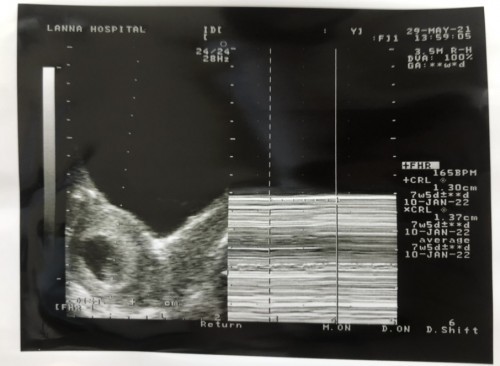

อยู่เชียงใหม่เหมือนกันค่ะ กำหนดคลอดเดือนกุมภาพันธ์ 2565 บ้านนี้แพ้หนักมาก น้องตามเกณฑ์ปกติค่ะ แต่แม่น้ำหนักไม่เพิ่มเลย 13 วีค ฝากลานนาเหมือนกัน ท้องแรกค่ะ ☺️